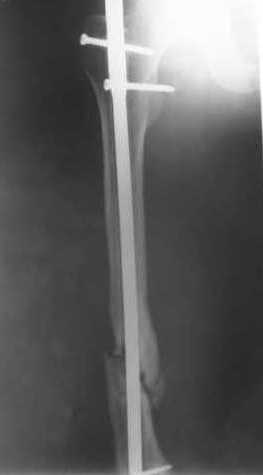

> Очень было бы любопытно посмотреть поэтапные Р-снимки с ЭОПа (хотя

В приложении пример, как их использовали после остеотомии бедра по поводу сросшегося с вальгусом перелома, чтобы не дать гвоздю уйти во внутренний мыщелок.

Да, действительно красивый клинический пример: виден вальгус до операции и последующая коррекция углового смещения на "полярах". Я так понимаю, что в вашей клинике есть возможность использовать различные фиксаторы. Почему не использовали DFN? Спицы какие используете? Киршнера или Илизаровские? С виду очень тонкие...